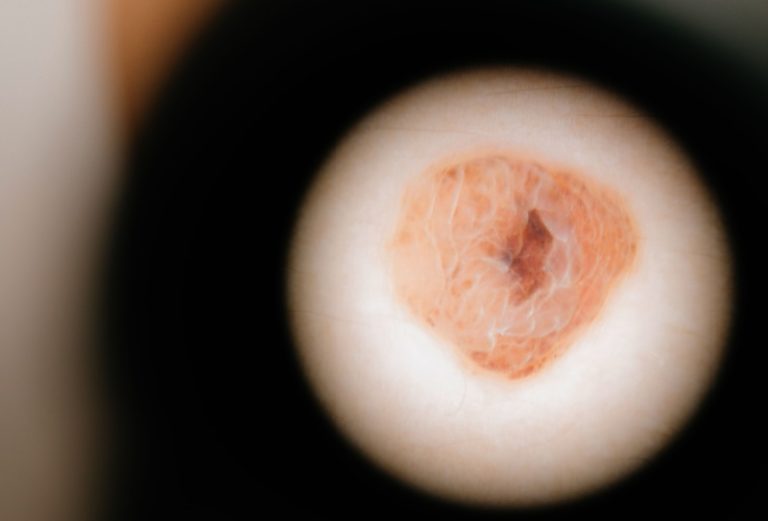

Chamamos de lesões vasculares da pele todas as anormalidades ou malformações dos vasos sanguíneos que podem ser percebidas através da pele. Elas podem ter diversas origens, tanto adquiridas quanto congênitas, e se manifestar em diferentes partes do corpo.

As lesões vasculares da pele podem se apresentar de formas distintas, entre as quais destacam-se:

- Hemangiomas ou tumores vasculares, que costumam surgir logo após o nascimento;

- Malformações vasculares e angiomas capilares, que podem se manifestar como manchas em diversos formatos na pele;

- Granulomas piogênicos, que se manifestam como nódulos vasculares que sangram facilmente;

- Telangiectasias, caracterizadas por dilatações visíveis de pequenos capilares.

O diagnóstico das lesões vasculares da pele é inicialmente clínico, com a avaliação das lesões em si e do histórico médico do paciente. Exames complementares, como a dermatoscopia e outros tipos de testes podem ser solicitados pelo médico para confirmar o diagnóstico e determinar exatamente o tipo de lesão.